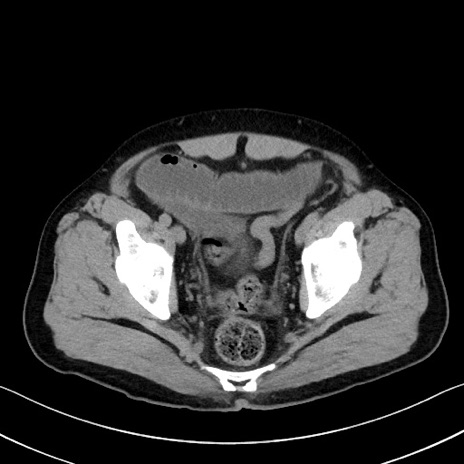

症例35(横断像)

【症例】70歳代 男性

【主訴】腹部膨満、嘔吐

【現病歴】昨日より腹部膨満感出現。本日増悪し、仙痛出現。嘔吐あり、受診。

【既往歴】糖尿病、胆摘後

【身体所見】BP 149/80mmHg、HR 74/min、BT 35.9℃、腹部:膨満、軟、圧痛なし。腸雑音減弱あり。上腹部正中切開瘢痕あり。

【データ】WBC 13500、CRP 1.72